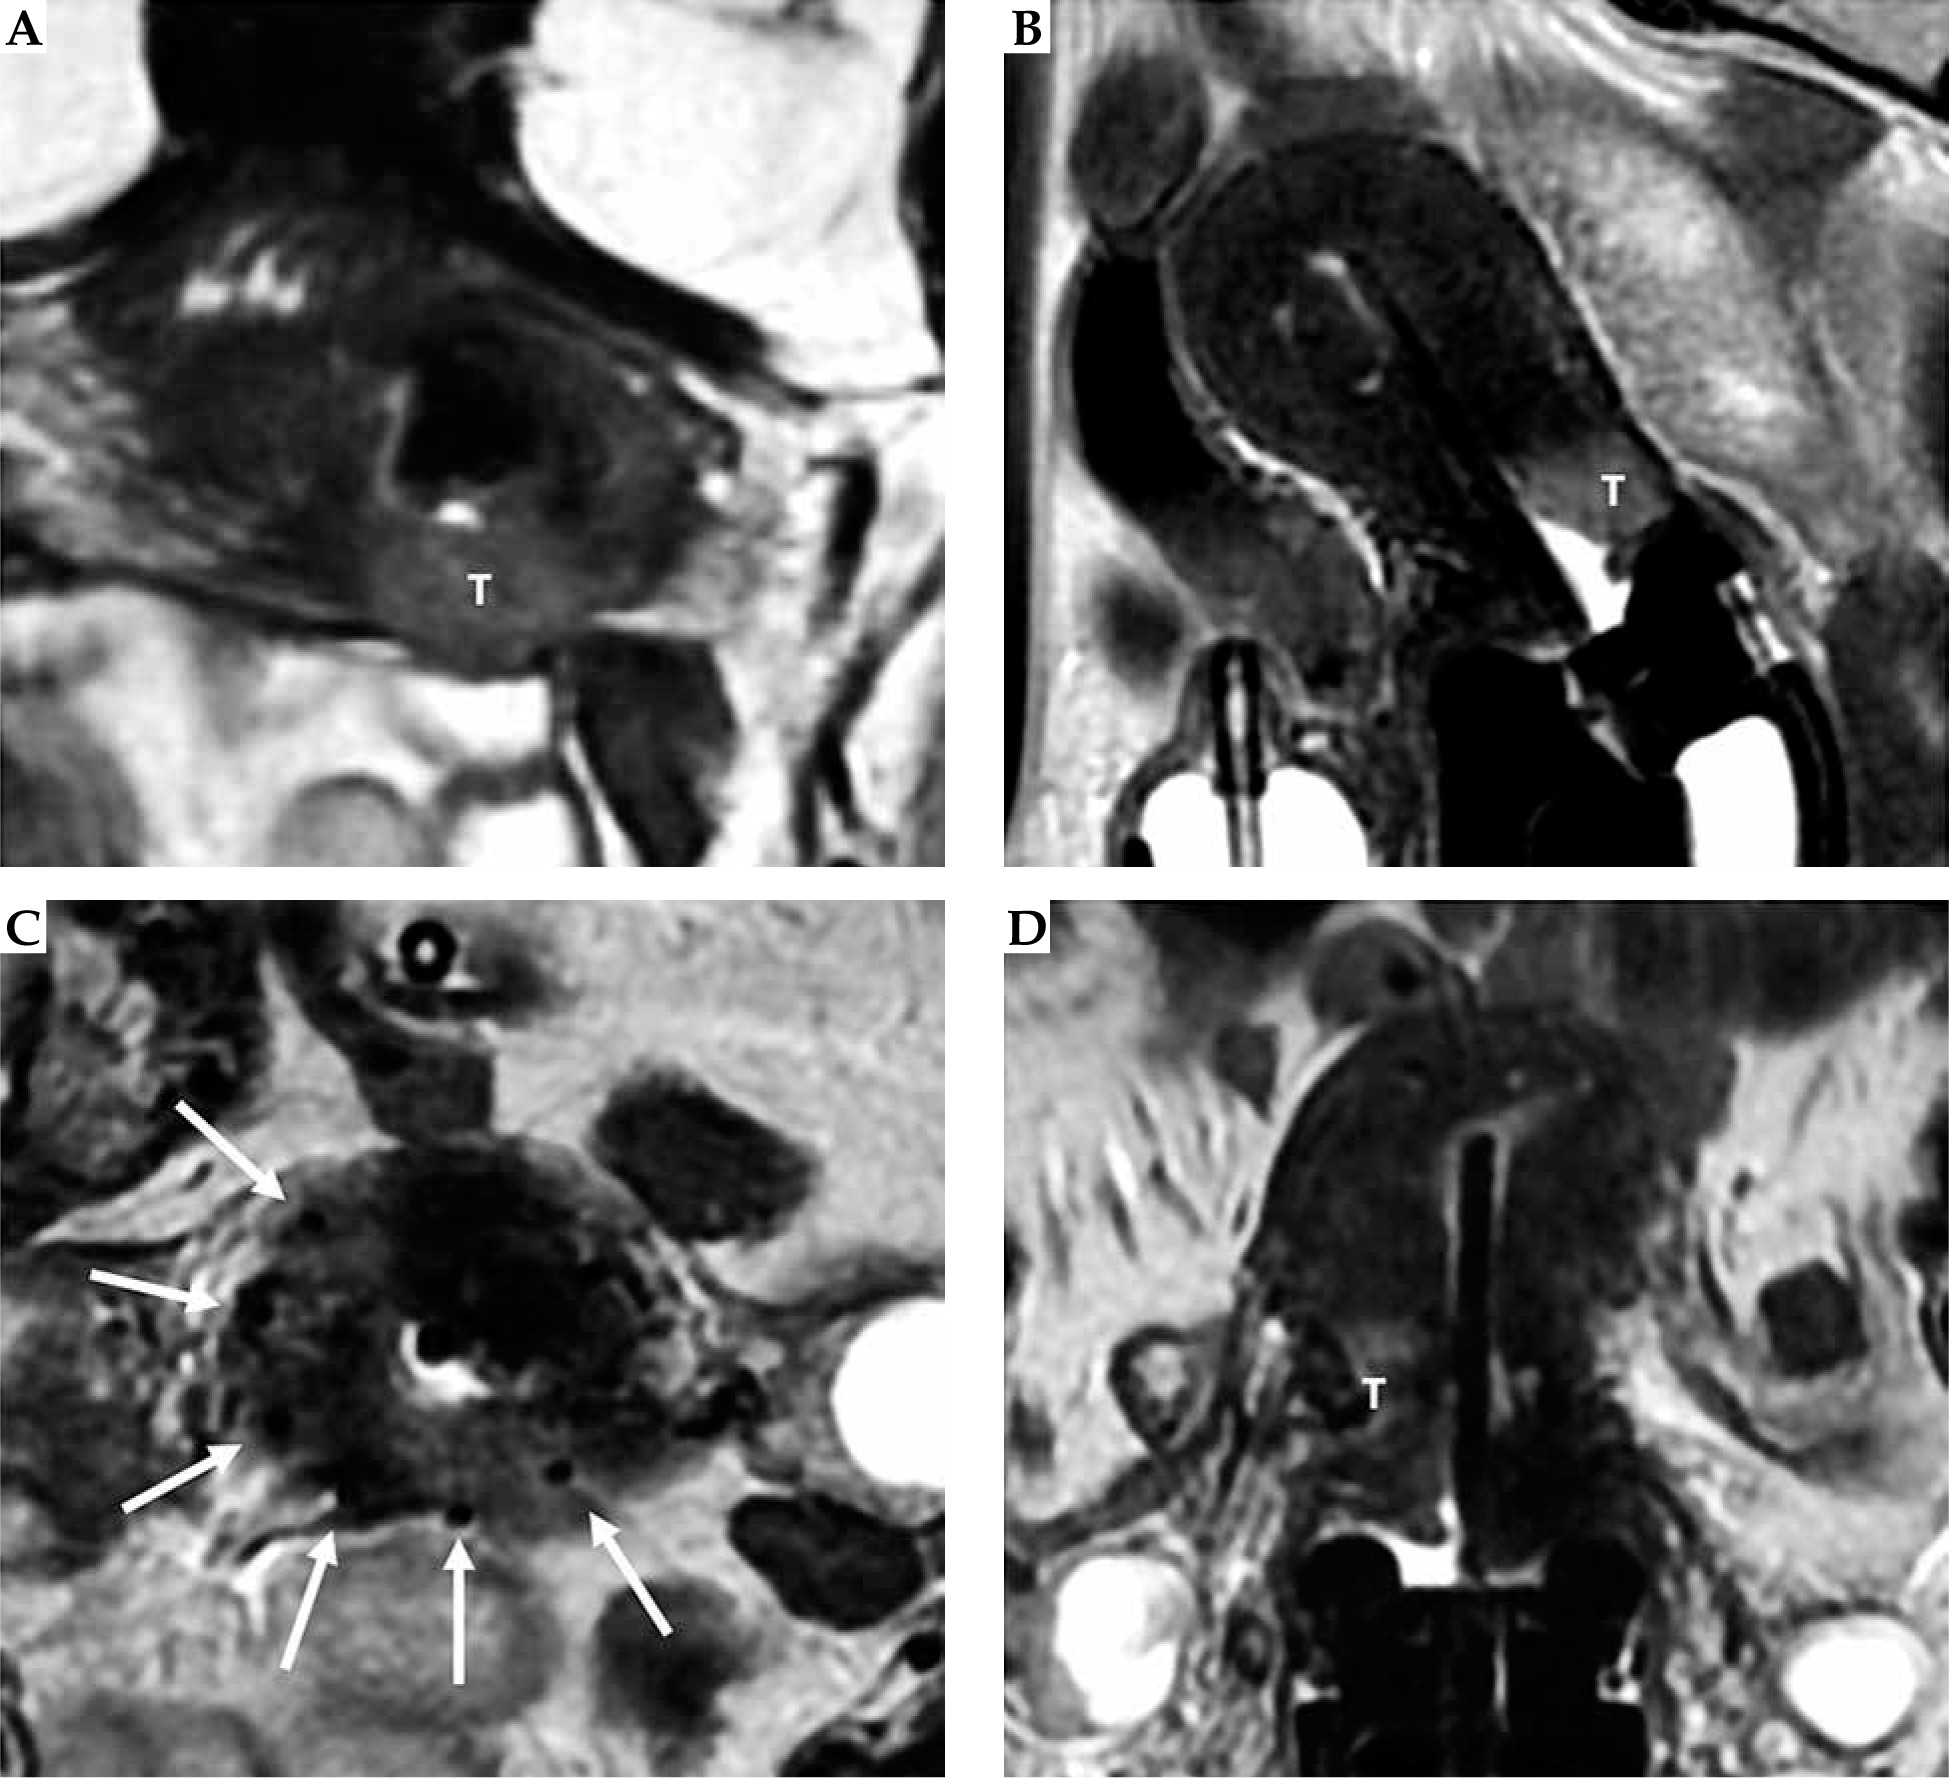

Fig. 10

34-year-woman with squamous cell cervical carcinoma. Post-external beam radiotherapy (EBRT) axial oblique T2-weighted image (A) indicates high signal-intensity residual tumor (T) extending in the right and posterior parametria. Post-applicator MRI (B-D) shows the relationship between the applicator and the residual tumor. In this case, interstitial needles (arrows in C) were placed to cover parametrial extension of the tumor